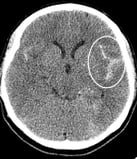

Tomografia computadorizada de crânio mostrando hemorragia intracerebral e hidrocefalia.

Tomografia computadorizada de crânio de mulher de 56 anos com hemorragia intracerebral e hidrocefalia.